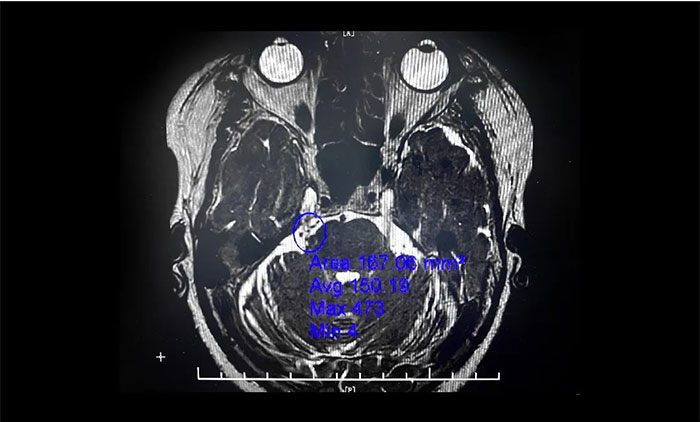

微血管減壓術(shù)是現(xiàn)代神經(jīng)外科典型的微創(chuàng)手術(shù)之一,僅通過患者耳后發(fā)際內(nèi)4-5cm的切口,于顯微鏡下探查三叉神經(jīng)走行區(qū),將所有可能產(chǎn)生壓迫的血管、蛛網(wǎng)膜條索都“松解”開,并將這些血管以Tefflon墊片與神經(jīng)根隔離。一旦責(zé)任血管被隔離,產(chǎn)生刺激的根源就消失了,三叉神經(jīng)核的高興奮性就會隨之消失,恢復(fù)正常。絕大多數(shù)患者術(shù)后疼痛立即消失,并保留正常的面部感覺和功能,不影響生活質(zhì)量。

▲ 右側(cè)三叉神經(jīng)與周圍小血管關(guān)系密切